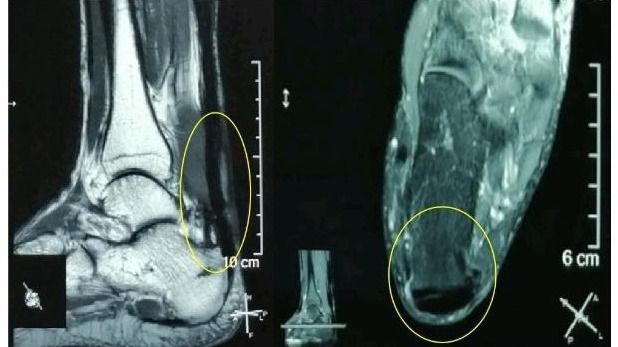

“感谢伍教授!我的跟腱疼痛、肿胀基本缓解了,踝关节活动也好多了,跑步也轻松了!”49岁的郑先生(化名)在电话中连声道谢。在跟腱断裂后,尽管做了修补术,但在半年多的时间里,他因跟腱疼痛、肿胀、踝关节活动受限而苦不堪言。幸好,在best365中国官方网站孙逸仙纪念医院康复科副主任伍少玲教授的帮助下,他接受了“超声引导下...